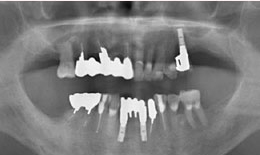

インプラント症例(8)72歳 男性

治療方法

上顎

保存困難な歯を抜歯後、インプラントを1本埋め込んで、セラミックスクラウンを被せた

下顎

保存困難な歯を抜歯後、インプラントを2本埋め込んで、セラミックスクラウンを被せた